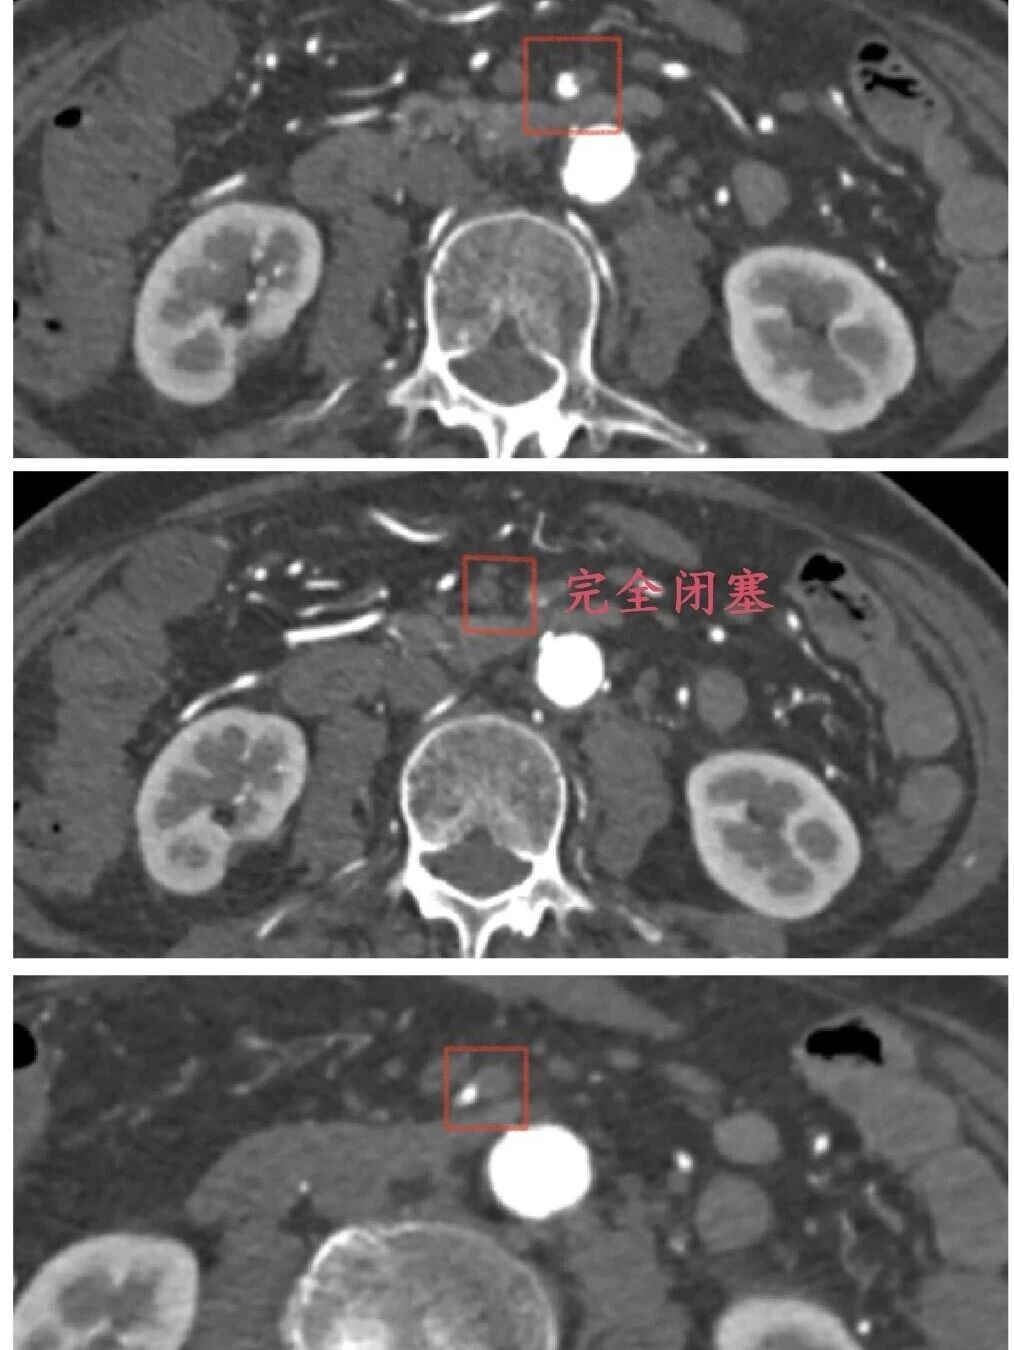

(资料图片)患者刘女士(化名)突发腹痛4.5小时,伴恶心呕吐、解稀便,紧急就诊于医院急诊科。刘女士有24年高血压、2型糖尿病病史,合并冠心病、心房颤动等多种基础疾病,还自行停用房颤抗凝药,身体基础条件差。急诊科接诊后迅速请血管外科会诊,冯涛副主任医师结合患者病史及症状,高度怀疑血管栓塞,建议完善肠系膜上动脉CTA检查。检查结果显示,患者肠系膜上动脉远段及胃左动脉、脾动脉近段动脉栓塞并脾梗死,同时合并腹主动脉、髂动脉多发狭窄等,病情危急,随时可能因肠管缺血坏死危及生命。

时间就是生命,鉴于患者高龄、基础病多,因传统开腹手术创伤大、风险高,术后并发症多,恢复时间较长。血管外科团队反复评估病情,与家属充分沟通后,决定采用微创介入手术治疗。科室迅速启动急诊手术绿色通道。术中,发现患者肠系膜上动脉起始处、距起始12cm处重度狭窄,15cm处完全闭塞,双侧肾动脉也有不同程度狭窄。随后,血管外科团队采用外周斑块切除系统清除肠系膜远端血栓,对重度狭窄处球囊扩张,操作精准、高效。术后造影显示,患者肠系膜上动脉管腔明显改善,血流量显著增加,无造影剂渗漏,手术成功,患者安返病房。